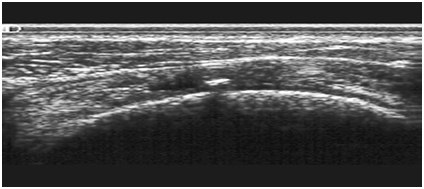

Op afbeelding ziet u een verklaring in een spier als gevolg van een microtrauma.